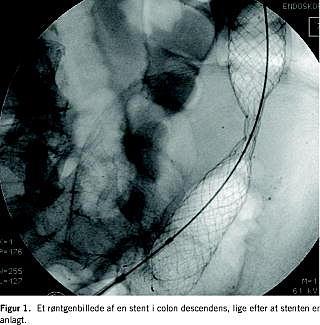

De første ti akutte stentanlæggelser blev foretaget på en operationsstue. Siden er de foretaget i endoskopiafsnittet under samme forhold som de elektive, hvis der ikke har været behov for generel anæstesi. Otte stent i den tidlige periode blev anlagt i generel anæstesi, men de fleste blev anlagt uden (n = 87) eller med let sedation (n = 67). Der blev ikke givet antibiotika i forbindelse med proceduren. Alle procedurer foregik under røntgengennemlysning med enten koloskop eller terapeutisk gastroskop afhængig af strikturens lokalisation. Stenten blev anlagt via skopet, langs skopet eller over en guidewire (Figur 1 ). Patienten lå i venstre sideleje, og skopet blev indført til strikturen. Hos de første patienter blev der taget biopsi fra tumoren, men dette er ikke længere rutine. Der blev foretaget røntgenkontrastmarkering med Lipiodol (Guerbet, Frankrig) i den normale slimhinde analt for strikturen, og en guidewire blev ført igennem strikturen og ca. 50 cm oralt. Ved problemer med passage af guidewiren blev der benyttet en Terumo-guidewire med blød spids (Radiofocus Guidewire, Terumo Europe, Belgien), der efterfølgende blev skiftet til en stivere guidewire over et injektionskateter. I den første fase var dilatation af strikturen nødvendig på grund af stentsystemets diameter. Med de sen ere stentsystemer (< 3,7 mm i diameter) var dilatation ikke nødvendig, hvorfor den øvre afgrænsning af strikturen blev visualiseret i gennemlysning ved hjælp af injektion af vandopløseligt kontrast igennem injektionskateteret. Ved strikturer i den nedre del af sigmoideum og analt herfor blev stenten anlagt over en stiv guidewire i gennemlysning, mens stent mere oralt blev anlagt gennem skopet i gennemlysning.